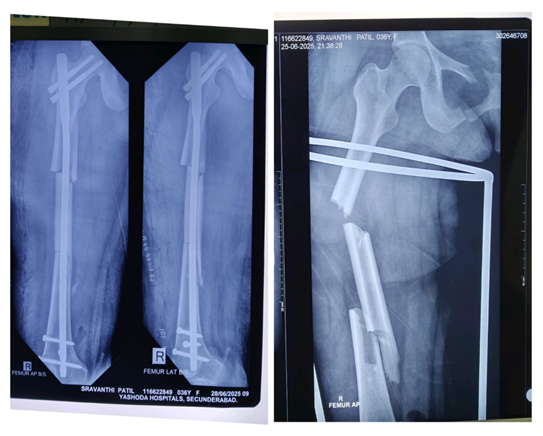

Before Treatment

The X-ray images show a comminuted fracture of the right femur shaft with displacement

There are multiple fragments (comminution) evident in the femoral shaft.The alignment is maintained surgically with an intramedullary nail and interlocking screws, indicating the patient had operative fixation (intramedullary nailing). The right side is indicated (R). The second image (on the right) shows the initial fracture pattern before surgical fixation, with the bone clearly broken into more than two pieces. This is a comminuted, displaced fracture of the right femoral shaft that has been treated with intramedullary nailing.